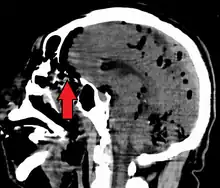

CT scans of patients with a tension pneumocephalus typically show air that compresses the frontal lobes of the brain, which results in a tented appearance of the brain in the skull known as the Mount Fuji sign.[1][2][3] The name is derived from the resemblance of the brain to Mount Fuji in Japan, a volcano known for its symmetrical cone. In typical cases, there is a symmetrical depression near the midline (such as the crater of a volcano), due to intact bridging veins.[3] Its occurrence seems to be limited to tension pneumocephalus (not occurring in pneumocephalus without tension).[4] The sign was first described by a team of Japanese neurosurgeons.[5]